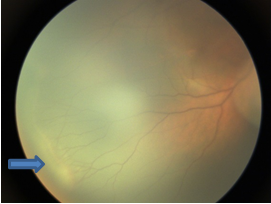

可疑家族性渗出性玻璃体视网膜病变